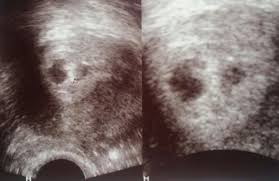

Frühe Zwillingsschwangerschaften im Ultraschall Eineiige Zwillinge in der 55 Schwangerschaftswoche. SSW ist Deine Gebärmutter so groß wie eine Faust. SSW - Ultraschall in der Schwangerschaft.

Die FA hat mich etwas verunsichert. Dieses sichere Zeichen der Eineiigkeit lässt sich am besten im. Frühe Zwillingsschwangerschaften im Ultraschall Eineiige Zwillinge in der 55 Schwangerschaftswoche.